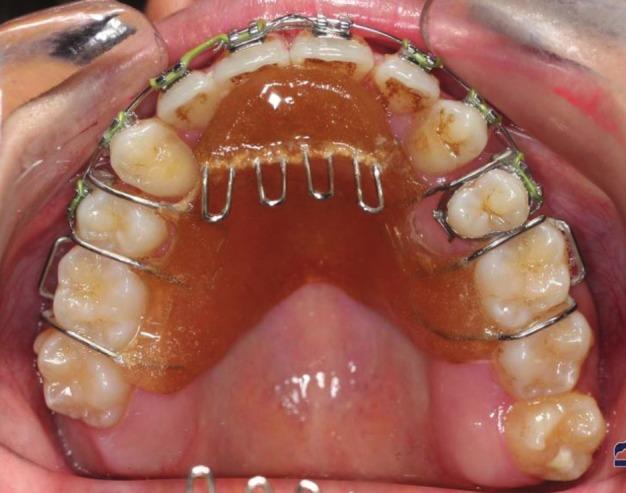

This case report presents a 22-year-old girl with class III malocclusion due to maxillary deficiency. The patient was referred for presurgical orthodontics; however, she rejected the surgery. This case was treated by means of Tongue appliance and slow palatal expansion, followed by lower fixed appliance, reverse chin cup, and upper fixed appliance. Tongue appliance and slow palatal expansion were used at the beginning of the treatment. After 6 months, reverse chin cup and lower fixed appliance were added. Six months later reverse chin cup was removed and upper fixed appliance was mounted. Positive overbite and over jet were achieved after 24 months of active treatment. Nasolabial angle also showed improvement. Nonsurgical treatment of adult class III patients is a difficult procedure; however, this patient was treated nonsurgically.

本病例报告介绍了一名22岁因上颌骨发育不足导致III类错牙合畸形的女孩。该患者被转诊接受术前正畸治疗;然而,她拒绝了手术。本病例采用舌弓矫治器和慢速腭扩展进行治疗,随后使用下颌固定矫治器、反向颏兜和上颌固定矫治器。治疗开始时使用舌弓矫治器和慢速腭扩展。6个月后,增加了反向颏兜和下颌固定矫治器。6个月后,移除反向颏兜并安装上颌固定矫治器。经过24个月的积极治疗,实现了覆牙合和覆盖正常。鼻唇角也有所改善。成年III类患者的非手术治疗是一个困难的过程;然而,该患者接受了非手术治疗。